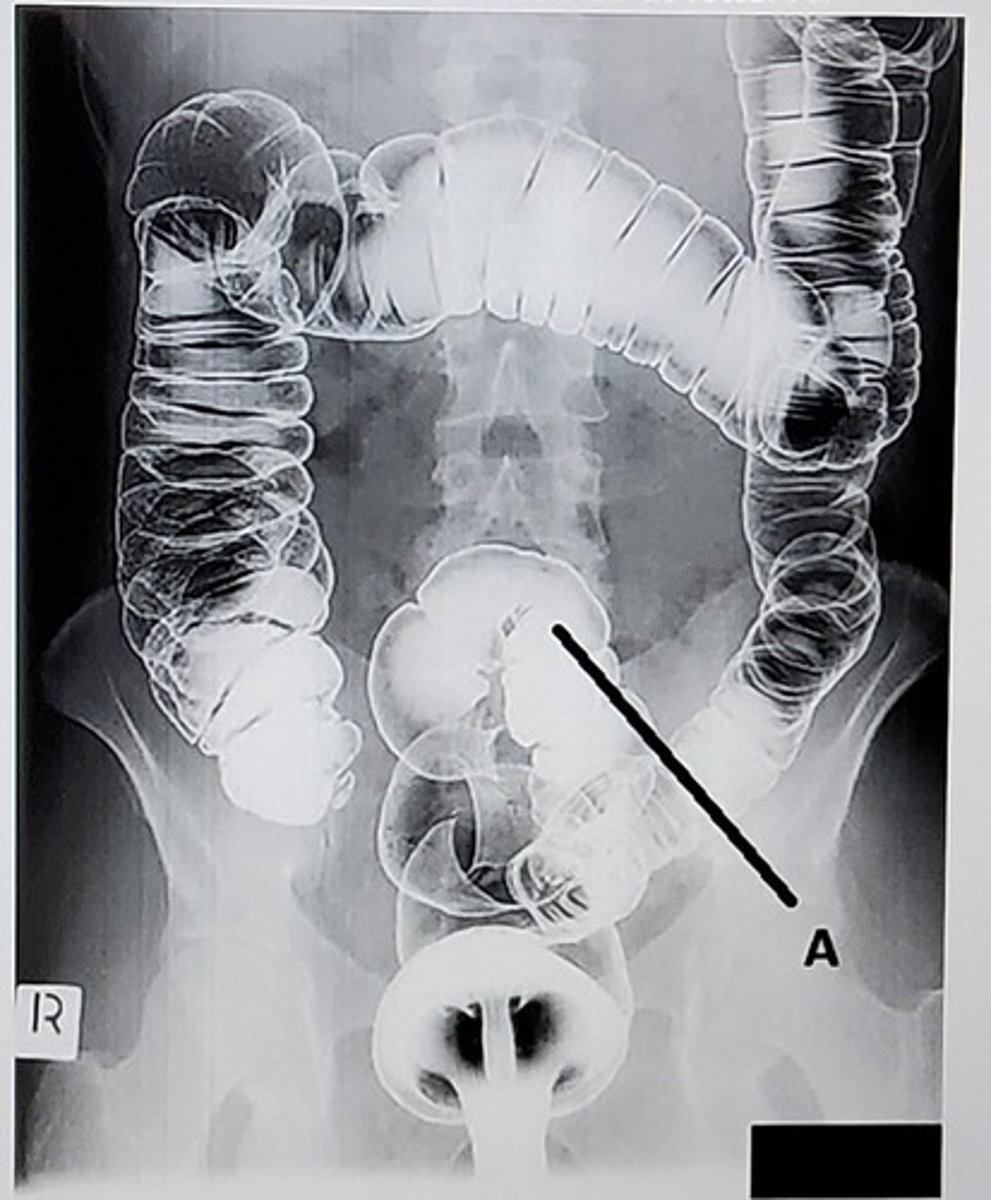

C. Sigmoid colon

What anatomic structure is labeled as letter A?

A. Cecum

B. Rectum

D. Descending colon